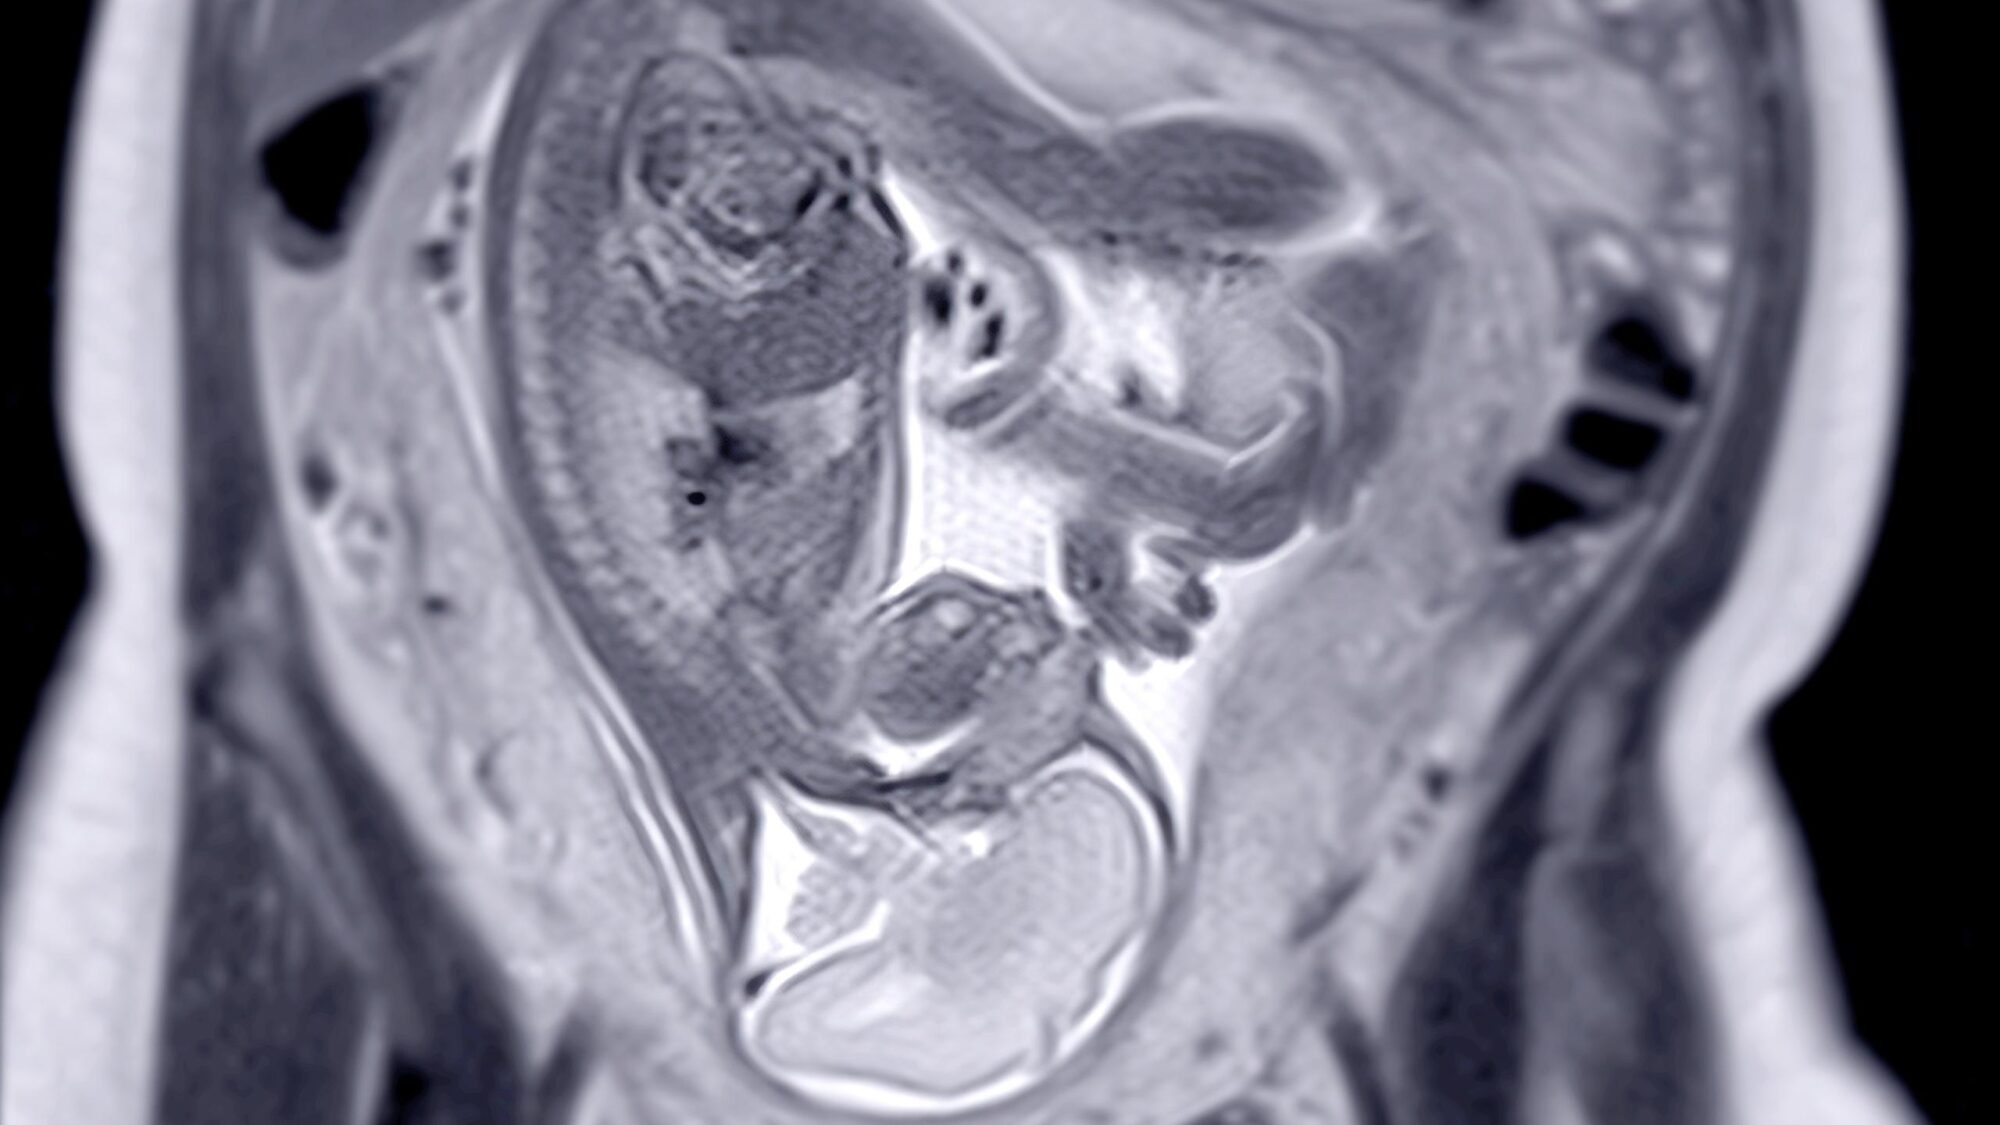

Chaque année, près de 20 000 enfants naissent avec une malformation congénitale en France, dont une large partie est détectée avant la naissance. Dans le cadre de l’évaluation des anomalies fœtales et placentaires suspectées, l’IRM fœtale, un examen complémentaire à l’échographie, permet de préciser le diagnostic. Une étude qualitative publiée dans la revue Radiography [1], menée par Teddy Medar, manipulateur radio à l’hôpital Necker, a analysé le ressenti et les retours d'expérience des manipulateurs radio impliqués dans la prise en charge des femmes enceintes subissant des examens d’IRM fœtale et exploré leurs méthodes pour faire face aux défis rencontrés lors de ces procédures.

Cet examen d’imagerie, d'une durée comprise entre 30 et 60 minutes, n’est pas sans difficultés pour les patientes enceintes qui ressentent souvent de l’inconfort et de l’anxiété ainsi qu'une importante charge émotionnelle. « Il a été démontré que le diagnostic prénatal de la pathologie fœ